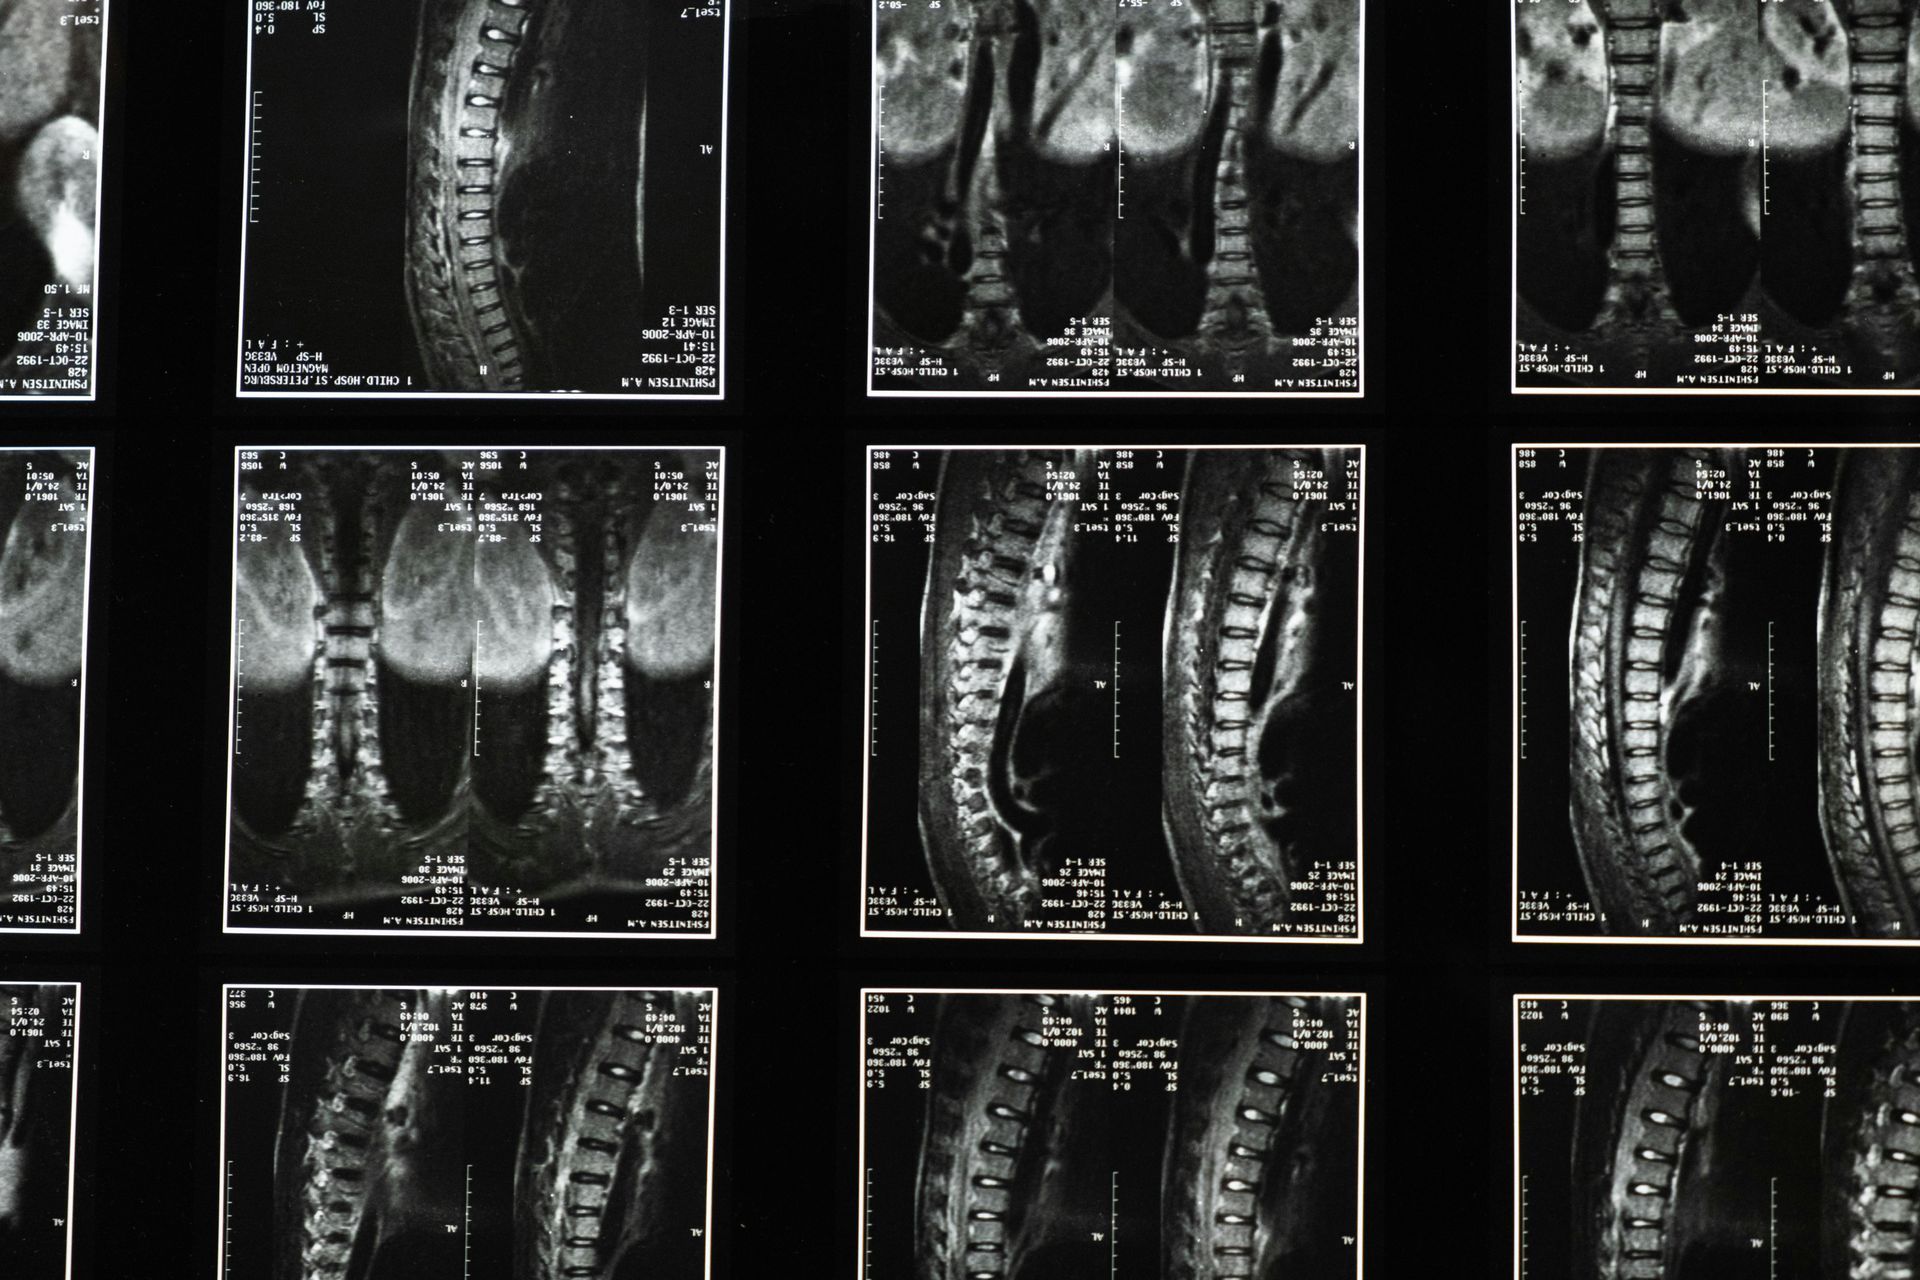

At Rainey Chiropractic, we believe in holistic healing. By targeting specific spinal regions, C1 on the left and C2 on the right, we initiated a transformative healing process. The results were astonishing. Not only did our patient's fatigue gradually dissipate, but they also began to regain the zest and zeal that had been missing from their life.